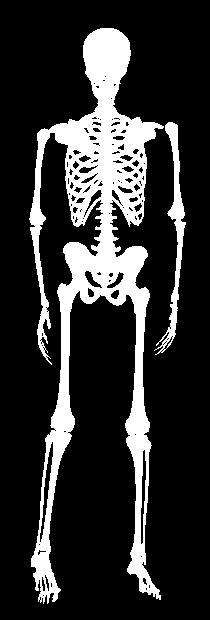

In this work, we address the problem of inferring the human anatomic skeleton, i.e. the bone shapes and locations, solely from surface observations. That is, we infer the bones from the skin. To that end, we learn a statistical model of the skeleton shape and its correlation with the skin surface (Fig. 1 left). Given a posed body, our method predicts the skeleton from the body shape, and poses it inside subject to anatomic constraints (Fig. 1 right).

5.4 Generalization to new poses